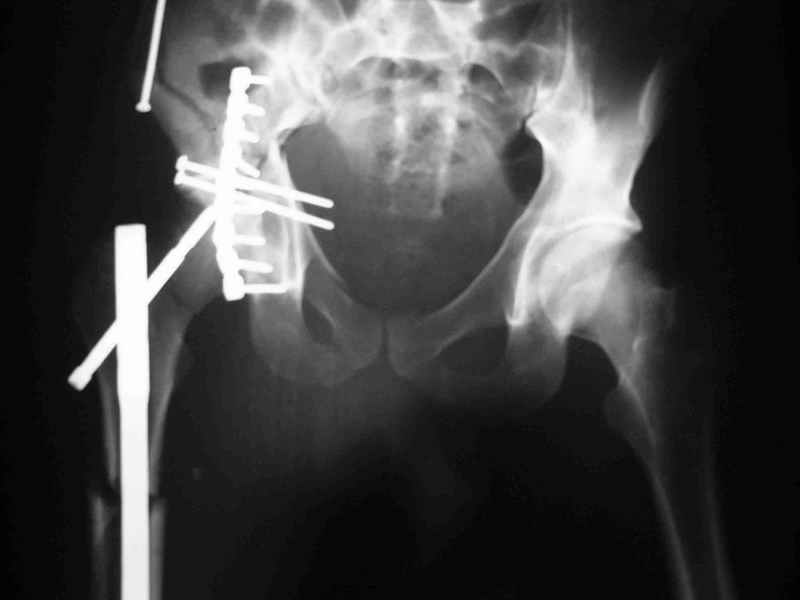

Re: Acetabular fracture

Djoldas kuldjanov, M.D. 02 Сентябрь 2004, 09:05

По снимкам:

Диагноз- перелом с вовлечением таза, разрыв правого сакро-илиак сочленения vertical shear injury, перелом крыла подвздошной кости?, перелом ацетабулум Т type или Both column?, перелом шейки бедра, перелом проксимального отдела бедра.

> Ваш окончательный диагноз?

перелом крыла правой подвздошной кости, перелом обеих колонн вертлужной впадины, двусторонний перелом лонных костей (С2.2) повреждение передних связок правого крестцово-подвздошного сочленения,

ипсилатеральный перелом шейки и диафиза бедра.

К сожалению, набора для ретроградного или антеградного реконструктивного штифтования в операционной нет, поэтому доставка заняла н-ное время. Вопрос, который возник у меня- по поводу оптимальной тактики хирургии: вся фиксация в один этап из расширенного доступа или последовательно сначала бедро и позже реконструкция впадины, комбинированный доступ к впадине отдельно к передней и задней колоннам или из расширенного илеофеморального одного доступа. Все-таки решил остановиться на одноэтапном подходе и спустя 5 дней (как раз и наборы привезли) из расширенного илеофеморального доступа сначала фиксировал реконструктивным штифтом Smith&Nephews бедро и

шейку (благо перелом шейки 2 типа -относительно стабильный) затем фрагмент крыла подвздошной кости Lag screw, далее пластина на заднюю колонну и винты в переднюю колонну.(с размерами и направлением винтов ошибка вышла:-((, но интраоперационно у меня была полная уверенность , что винты *ушли* в лонную кость).

Еще раз спасибо за комментарии и готовность помочь с имплантами. Постоп картинки в приложении,